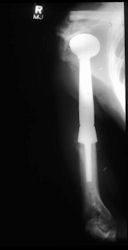

Examples of radical limb sparing surgeries for osteosarcomas in various anatomic locations (distal femur, proximal tibia, proximal humerus, scapula)

In each case, the tumor and bone from which it arose were resected. This required meticulous dissection, mobilization and preservation of adjacent pertinent neurovascular structures. In each case presented here, the defect was reconstructed with a special modular segmental tumor prosthesis. This also replaces the adjacent joint in many instances.

Proximal Humerus: Radical Limb Sparing Extra-Articular Resection and Prosethetic Reconstruction